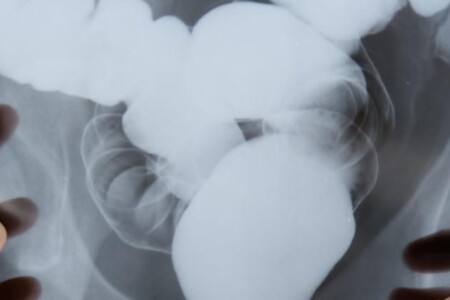

Příčiny gastroenteritidy jsou spletité. Zdaleka nejčastěji je onemocnění vyvoláno infekcemi, zejména těmi, které způsobují alimentární nákazy. Bakterie, které kontaminují potravu, mohou vyvolat onemocnění jedním ze dvou způsobů: buď napadnou přímo sliznici zažívacího traktu, nebo vyprodukují toxiny (jedy), které zažívací trakt dráždí nebo znemožňují normální trávicí pochody. Výsledkem je vždy zánět sliznice žaludku a střev. Mohou se zde vytvořit malé vřídky, které mohou krvácet, způsobit ztrátu vody, solí a bílkovin, jež tělo potřebuje. Gastroenteritida se někdy objeví jako epidemie šířící se od jedné osoby k druhé podobně jako třeba rýma. V těchto případech mají nemoc na svědomí většinou viry. Jako gastroenteritida se také může projevit mírnější forma úplavice vyvolaná bakteriemi rodu Shigella. Tato infekce se často šíří v dětských kolektivech přímým kontaktem, zejména když se příliš nedbá na dodržování hygieny.